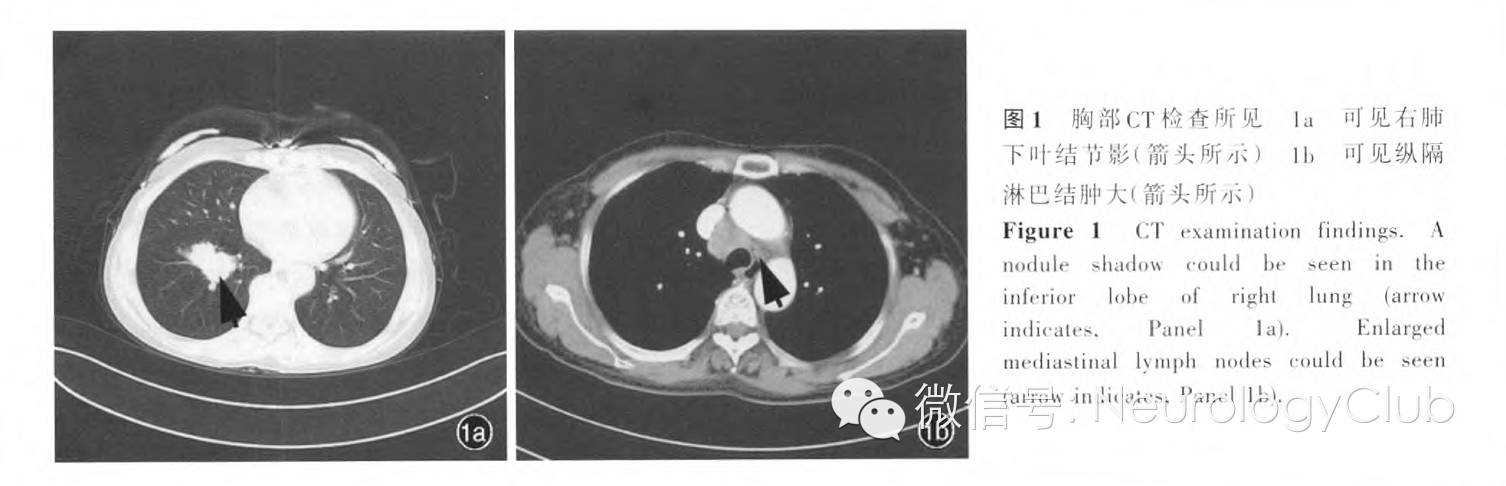

入院后辅助检查 血尿便常规及便潜血试验、肝肾功能试验、血清脂质、感染四项[丙型肝炎病毒抗体、乙型肝炎病毒表面抗原、梅毒螺旋体(TP)抗体、人类免疫缺陷病毒(HIV)抗体和抗原初筛]均未见明显异常;肌酸激酶(CK)为28U/L(18-198U/L);凝血功能检测D-二聚体0.56mg/L(0-0.55mg/L)。内分泌代谢相关检查:甲状腺功能试验无明显异常;空腹血糖3.40mmol/L(3.60-6.10mmol/L),糖化血红蛋白(HbA1c)5.40%(4.50%-6.30%)。自身免疫反应相关检查:抗核抗体(ANA)谱(19项)中抗干燥综合征A抗体(SSA)呈弱阳性、血清抗神经节苷酯GMl抗体呈阴性反应;M蛋白相关检查血清蛋白电泳、免疫固定电泳、血清轻链未见明显异常。肿瘤相关检查:肺癌标志物筛查胃泌素释放肽前体(ProGRP)573.80pg/ml(0-50pg/ml)、细胞角蛋白19片段(CYFRA21-1)11.22ng/ml(0-3.50ng/ml)、神经元特异性烯醇化酶(NSE)16.30ng/ml(0-16.30ng/ml)、组织多肽特异性抗原(TPS)195.05U/L(0-80U/L)。胸腹部增强CT显示,右肺下叶结节影(考虑恶性肿瘤可能);纵隔多发肿大淋巴结(考虑转移可能,图1)。腹部、子宫和双侧附件、乳腺超声均无明显异常。

神经科主治医师 患者为中年女性,呈隐匿发病,病程约3.50个月。临床主要表现为双下肢无力,逐渐出现双上肢无力、眼外肌及延髓肌症状,伴易疲劳现象,晨轻暮重;溴吡斯的明治疗后症状好转,既往有20年吸烟史。查体神志清楚、语言流利,各向眼动充分,无复视,双上睑不遮瞳,咽反射存在,其余脑神经检查未见异常。四肢肌张力正常,双侧桡骨膜反射、跟腱反射对称存在,余腱反射消失。双上肢近端肌力5-级、双下肢近端肌力4+级.四肢远端肌力5级;深浅感觉对称存在,共济运动尚可;可完成3个蹲起动作,双睑用力睁闭30次后双睑遮瞳1/2;双上肢可平举2分钟。辅助检查:外院肺部CT显示纵隔淋巴结肿大,但肺内无异常结节影。我院电生理学检查:神经传导速度显示下肢运动神经波幅降低;肌电图呈肌源性损害;低频重复神经电刺激波幅递减、高频电刺激波幅递增。定位诊断:(1)四肢无力、眼外肌无力,延髓肌无力,伴易疲劳现象,结合重复神经电刺激呈低频递减、高频递增,肌电图为肌源性损害,神经传导速度下肢波幅降低、上肢亦在正常值低限,且对溴吡斯的明治疗有效,故定位于神经-肌肉接头处损害;肌源性损害可能为继发性改变。(2)尿急、尿频,偶有尿失禁,定位于自主神经。定性诊断:患者为中年女性,呈亚急性病程.临床症状主要以运动系统症状为主,双下肢率先受累,而后累及眼外肌,并伴自主神经功能障碍,近端腱反射消失,溴吡斯的明治疗有效,重复神经电刺激显示高频递增,考虑Lambert-Eaton肌无力综合征:该综合征有副肿瘤性和非副肿瘤性之分,副肿瘤性常见于小细胞肺癌。该例患者发病之初外院胸部CT未发现肺内占位性病变,但纵隔淋巴结肿大。有部分小细胞肺癌患者影像学先检出纵隔淋巴结转移灶,继而发现肺内原发灶。因此可行胸腹部增强CT扫描,必要时还可行高分辨力CT检查。该例患者肌无力症状呈现波动性、易疲劳现象,且溴吡斯的明治疗有效,需注意与重症肌无力相鉴别。但有眼外肌受累的重症肌无力患者多白眼外肌发病,逐渐进展至全身,而该患者以下肢发病.最后累及眼外肌,不符合重症肌无力的典型表现,且重复神经电刺激显示高频递增,不支持重症肌无力诊断。需进一步完善肿瘤标志物筛查、胸腹部增强CT检查,以及妇科超声检查,并应进一步行甲状腺功能试验。

呼吸科医师 患者为中年女性,有20年吸烟史,无明显感染征象。入院后增强CT显示右肺下叶结节影、纵隔淋巴结肿大,诊断需首先考虑肺部肿瘤,倾向小细胞肺癌。小细胞肺癌的副肿瘤综合征征象一般可早于肿瘤本身,该例患者发病时外院胸部CT未发现肺内占位性病变,但可见纵隔淋巴结肿大。小细胞肺癌易发生淋巴结转移,考虑纵隔淋巴结肿大为小细胞肺癌淋巴结转移,且外院未行高分辨力CT检查,易遗漏肺内原发灶。为进一步明确诊断,建议完善肺组织活检,行支气管镜活检。明确病理类型和疾病分期后,制定合理的治疗方案。